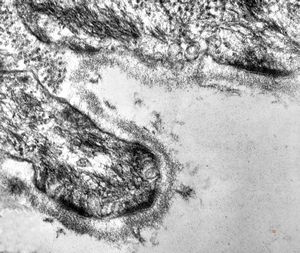

F,68y. | collagenous and elastin fibers from corium